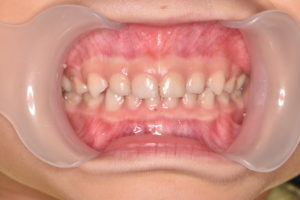

受傷から1ヶ月半

少し歯の変色は残っていますが、元の色に戻ってきました。

痛みもなく、レントゲン所見も異常がないため、固定していたワイヤーを除去し更に経過観察を行います。